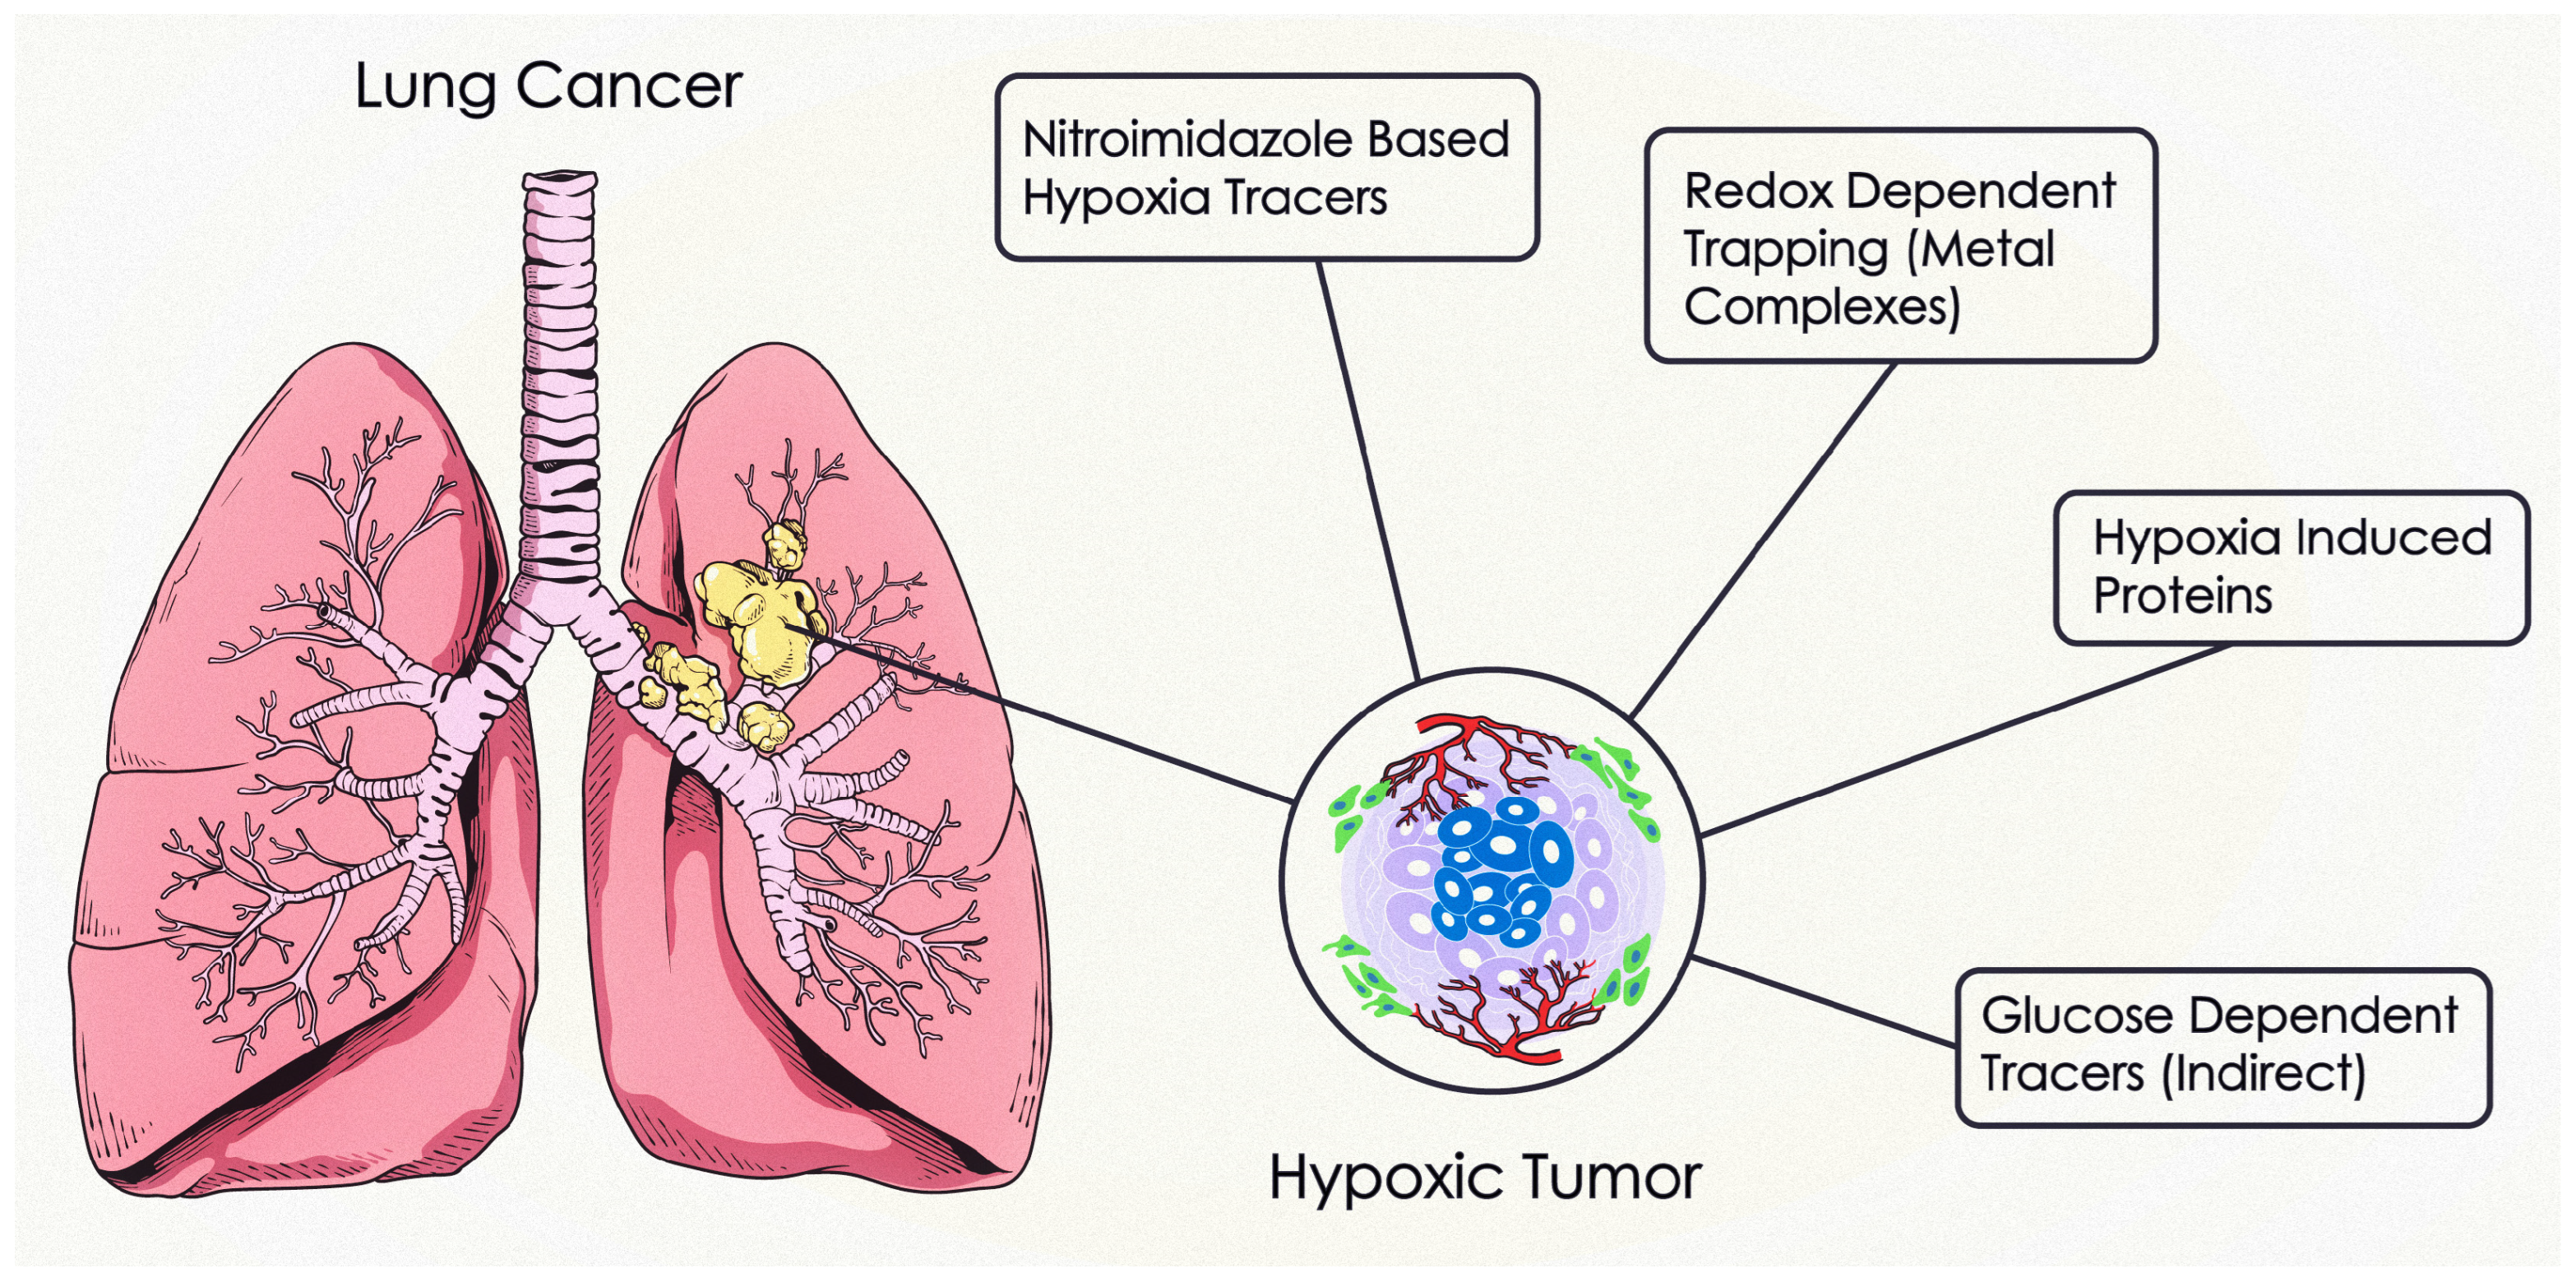

2. Pathophysiology of Hypoxia

3.3. Hypoxia PET Imaging